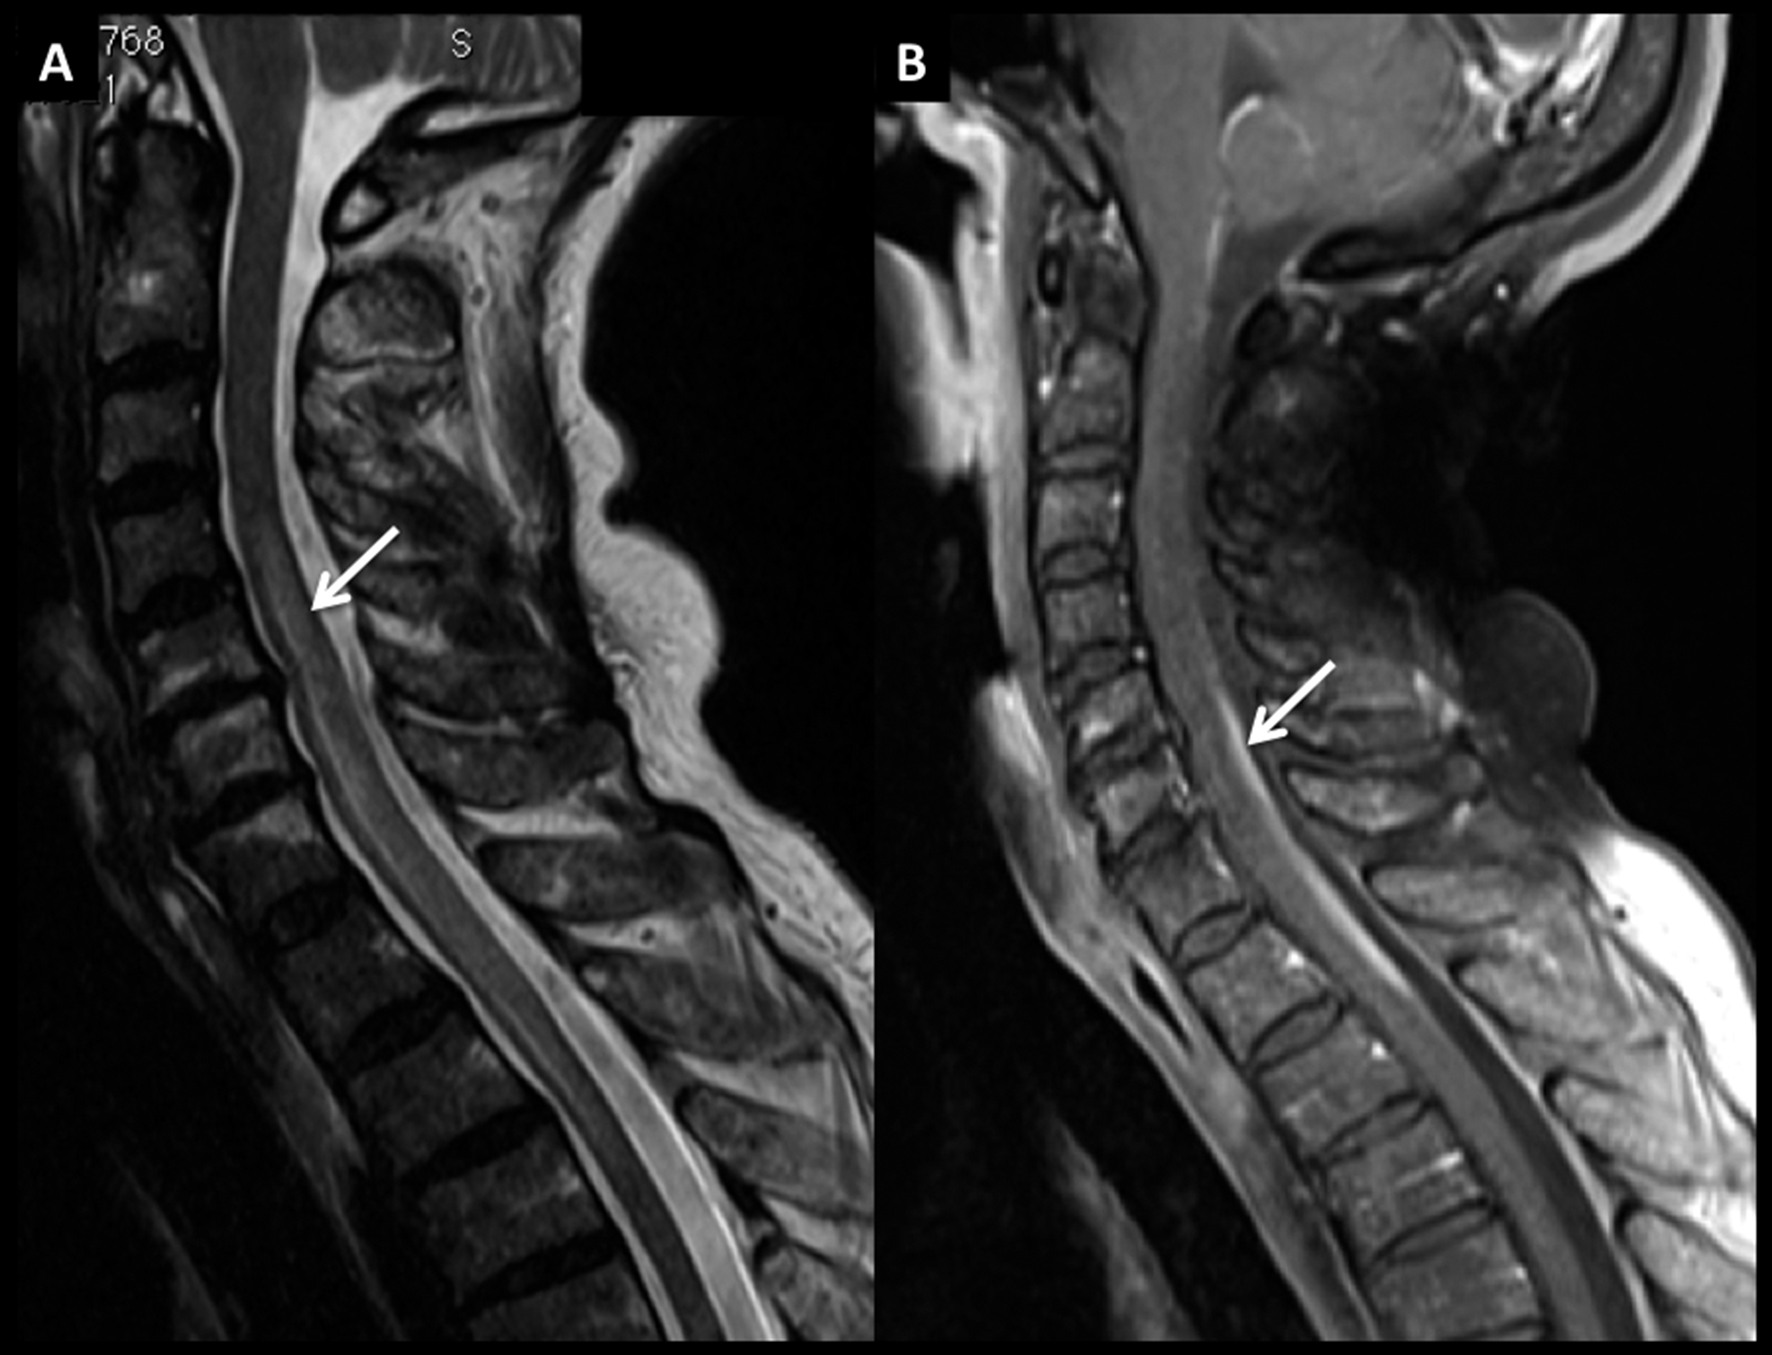

Figura 8

LNH, lesión medular, compromiso primario.

Paciente de 54 años con síndrome medular de instalación progresiva. En RM se identifica lesión medular cervical con ensanchamiento focal de varios segmentos, con alta intensidad de señal en secuencia T2 (A) y realce lineal, intenso, en secuencia T1 post-gadolinio (B).

LNH, lesión medular, compromiso primario. (cont)

En secuencia T2 en el plano axial (C) la alteración es heterogénea, centro-medular. Se decidió realizar biopsia de este proceso y el estudio histopatológico confirmó el diagnóstico de linfoma. Luego de la valoración sistémica no se evidenció compromiso asociado en otros territorios por lo que el diagnóstico final fue de LNH primario.